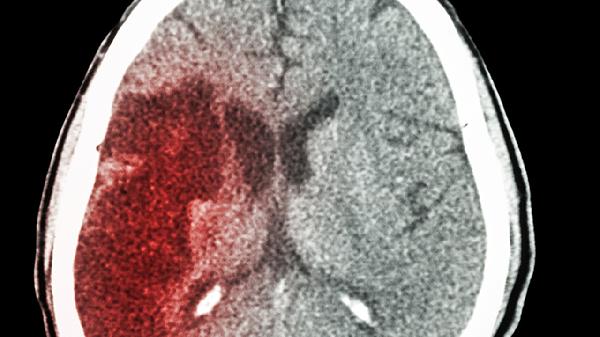

宝宝摔后脑出血的症状主要有意识模糊、频繁呕吐、瞳孔不等大、抽搐、嗜睡等。脑出血可能与颅骨骨折、脑血管损伤等因素有关,通常表现为头痛、哭闹不安等症状。建议及时就医,积极配合医生治疗。

宝宝摔后脑出血可能出现意识模糊,表现为对周围环境反应迟钝或无法辨认亲人。这种情况可能与颅内压增高或脑组织损伤有关。家长需立即带宝宝就医,医生可能会建议进行头颅CT检查以明确出血部位和程度。治疗上可能需要使用甘露醇注射液降低颅内压,或采取手术清除血肿。

摔伤后出现双侧瞳孔大小不等是脑出血的危险信号,提示可能存在脑疝。这种情况常伴随对光反射迟钝或消失。家长发现后应立即送医,途中避免移动宝宝颈部。治疗上可能需要紧急使用甘露醇注射液脱水降颅压,严重时需进行去骨瓣减压术。